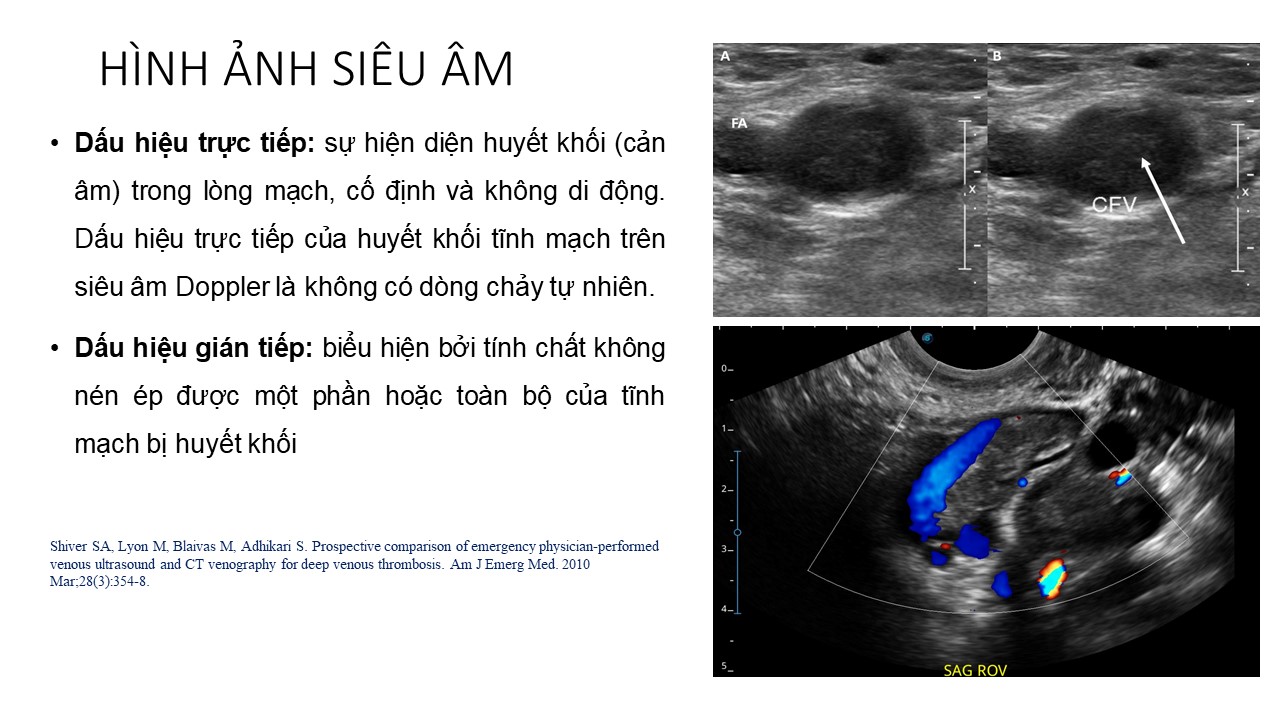

Dự phòng huyết khối tĩnh mạch sâu và thuyên tắc phổi trong sản khoa Thách thức và giải pháp